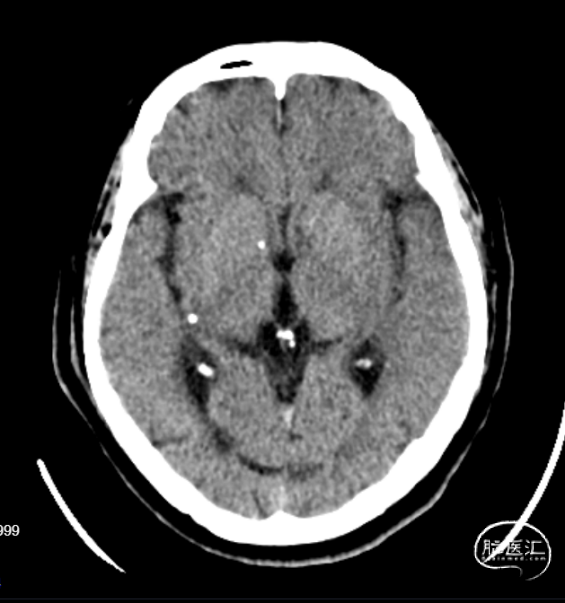

急诊CT平扫:未见颅内出血。

CTP:左侧丘脑、基底节区、额叶、颞叶、顶叶、枕叶见异常灌注区。

全脑核心梗死区(CBF<30%)体积为54.95mL,低灌注区(Tmax>6.0s)体积为183.95mL,Mismatch体积为129.00mL,Mismatch比值为3.35。

CTA:左侧颈内动脉、左侧大脑中动脉闭塞。